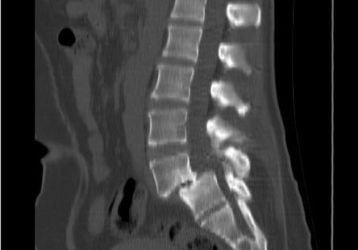

Лечение спондилолистеза поясничного и шейного отделов позвоночника

Что такое спондилолистез l5 s1, с5, с5 с6. Лечение диагноза медикаментами, упражнениями и хирургическими способами крестцового отдела.